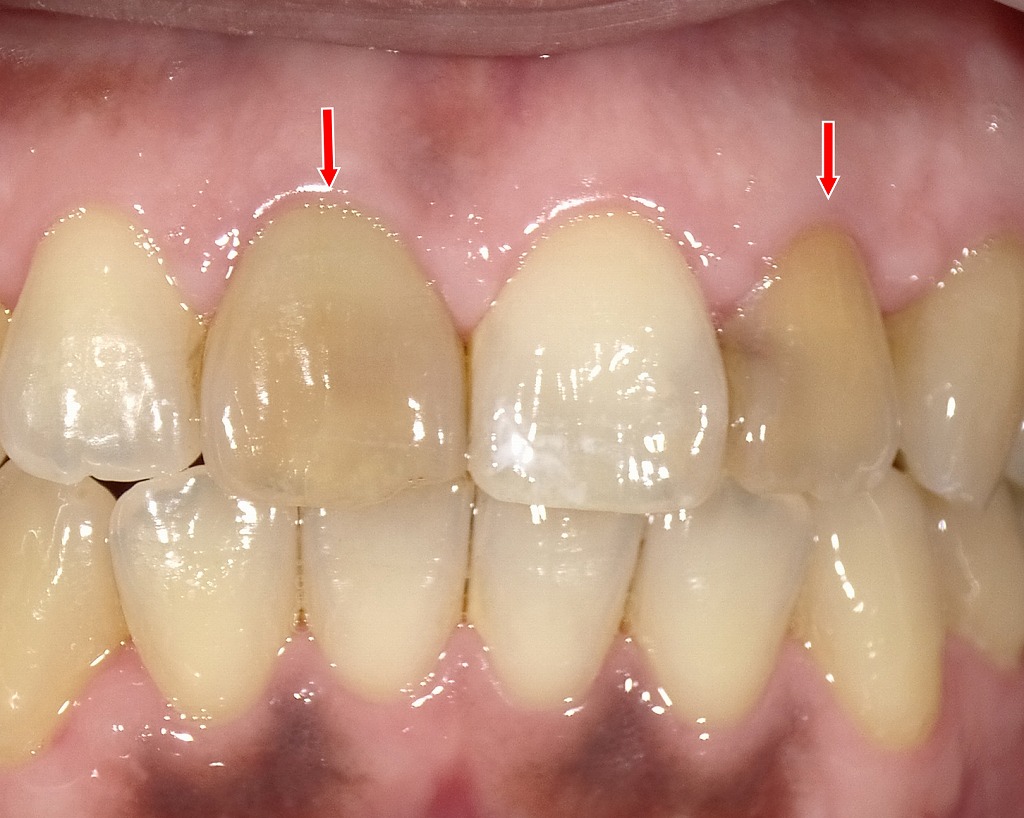

シェードテイキング

この写真は、ホワイトニング後に右上1番のオールセラミッククラウン製作を予定している症例のシェード確認(色合わせ)を行っている場面です。

手前にあるシェードガイドは「A1」で、一般的な自然歯の中でも比較的明るい色調を示します。しかし、周囲のホワイトニング後の歯はA1よりさらに白く、透明感のある仕上がりになっていることがわかります。

このため、最終的なオールセラミッククラウンは、ホワイトニング後の歯列全体と調和するよう、A1より明るいシェード(例:BL1~BL2系統)が選択される見込みです。

歯肉の状態も健康的で、最終補綴後には自然で審美的な前歯部の仕上がりが期待できます。